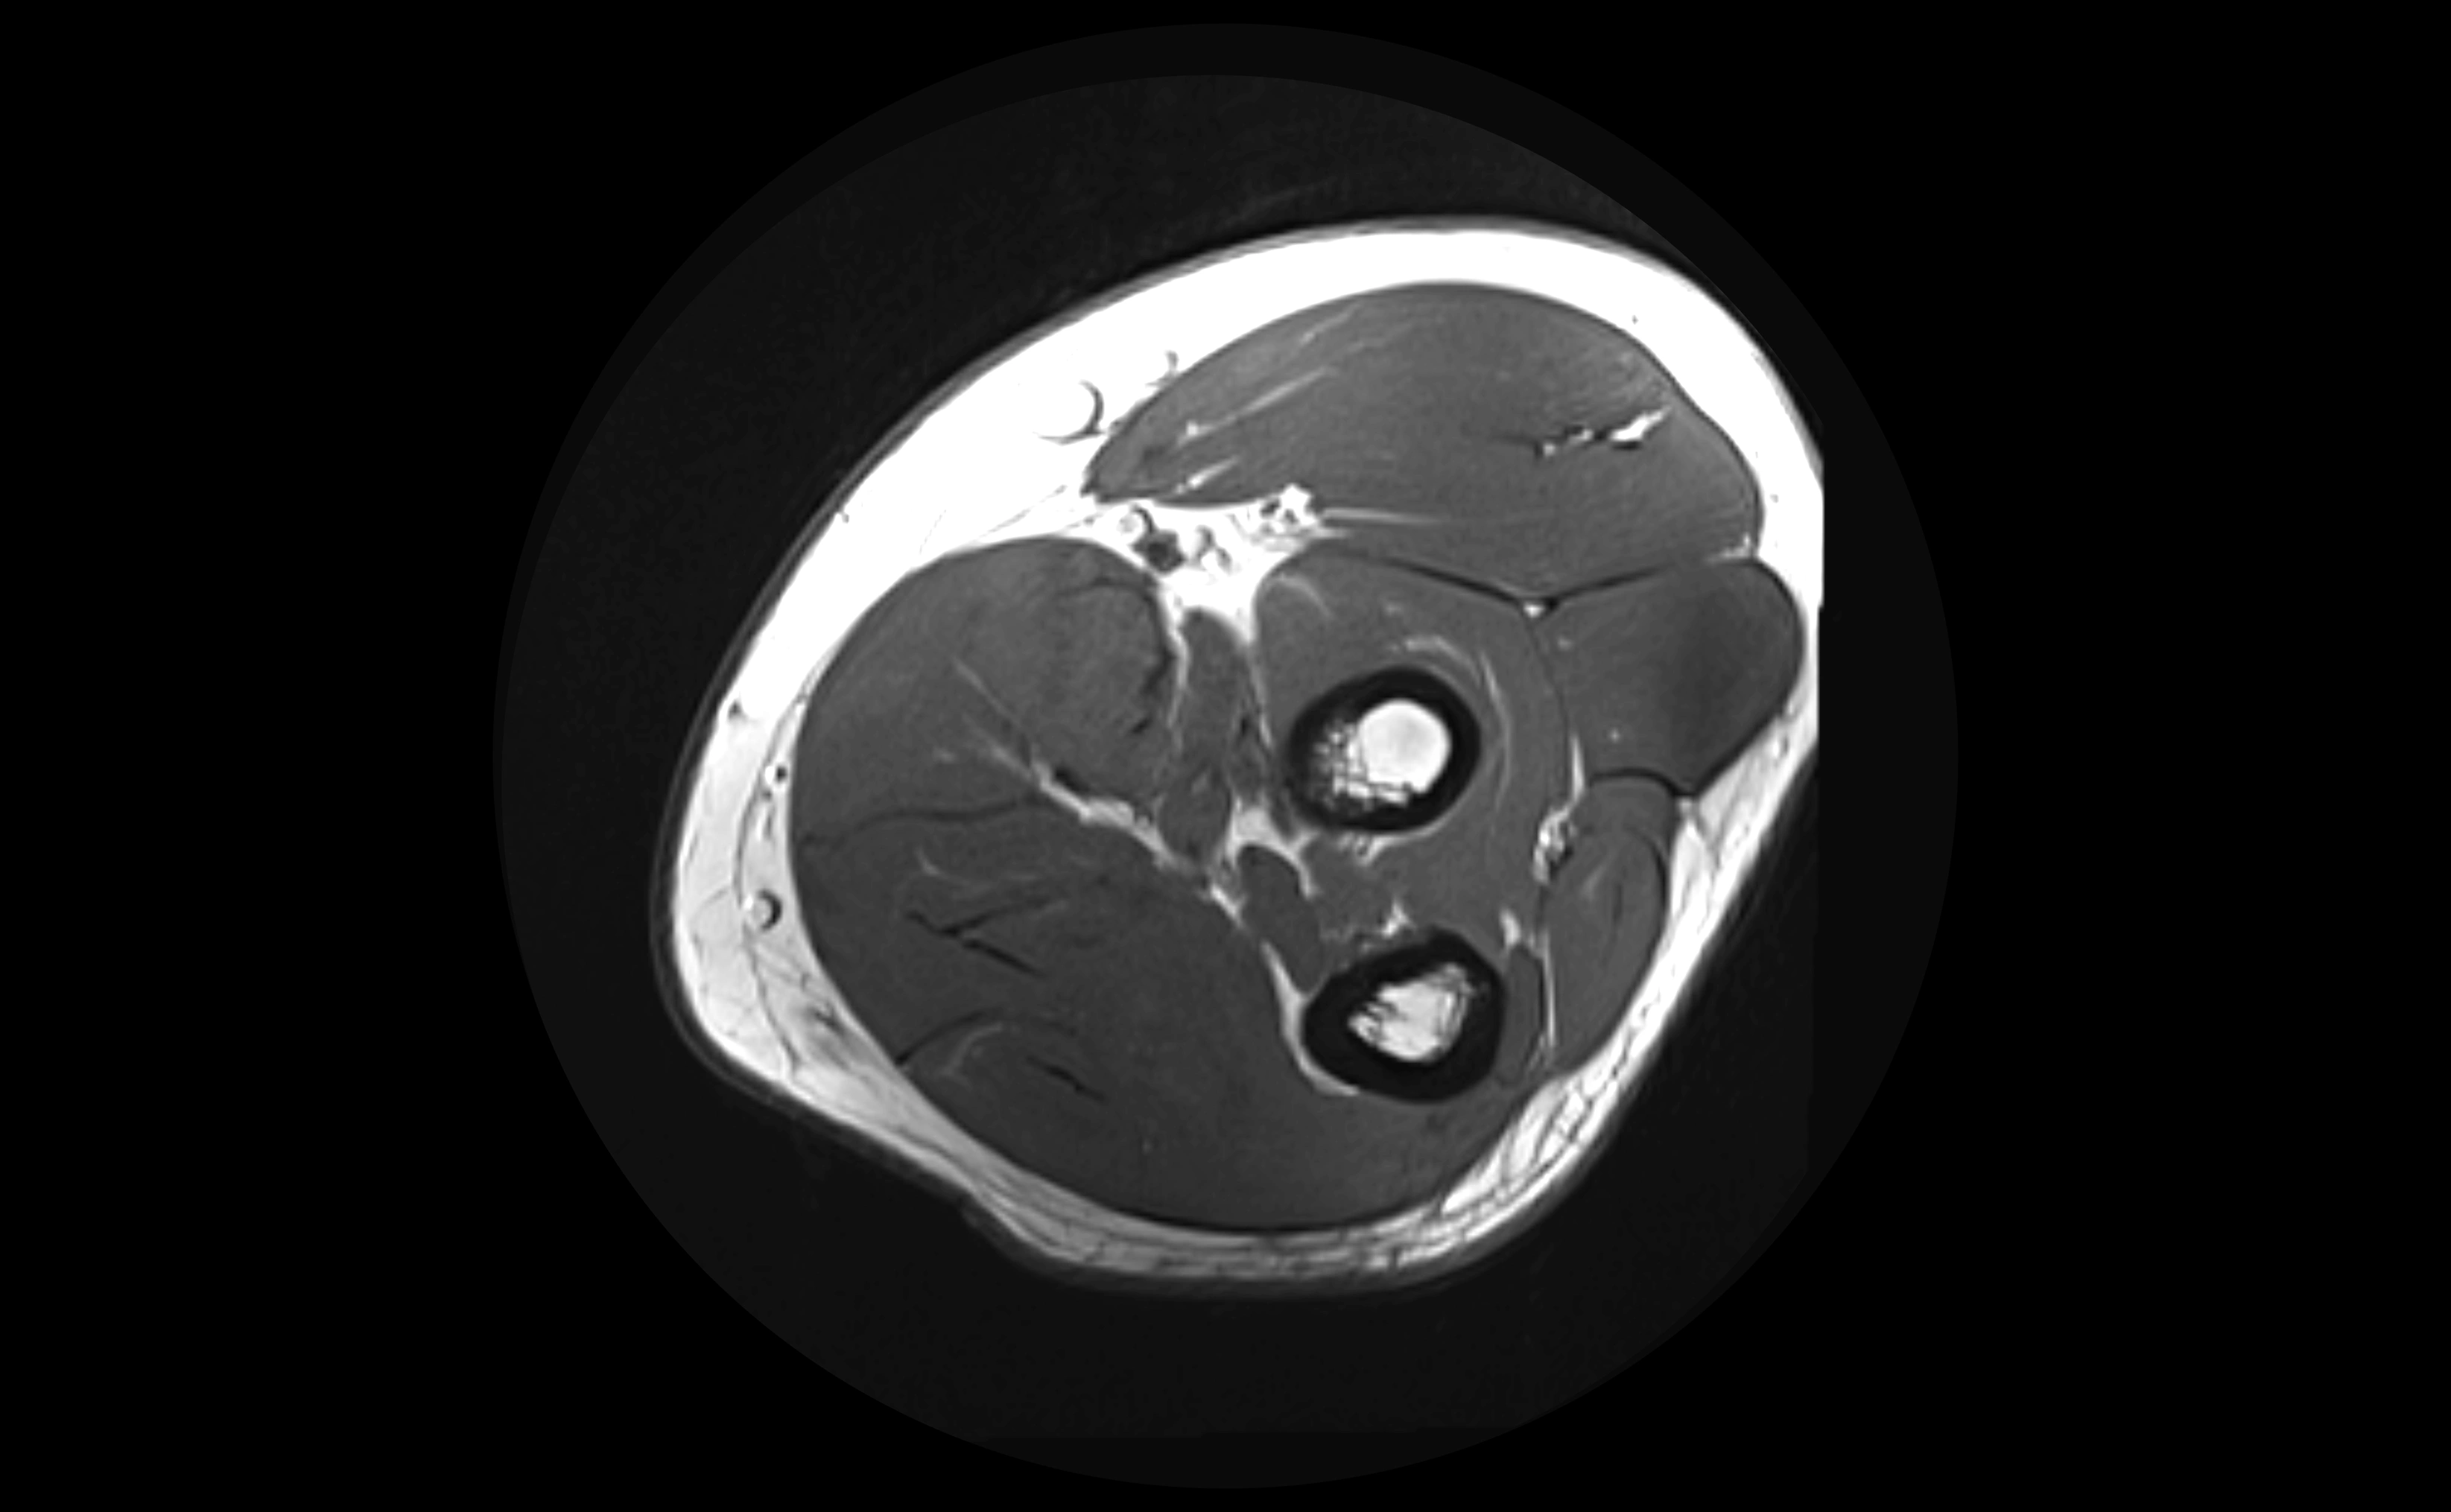

MRI images

image